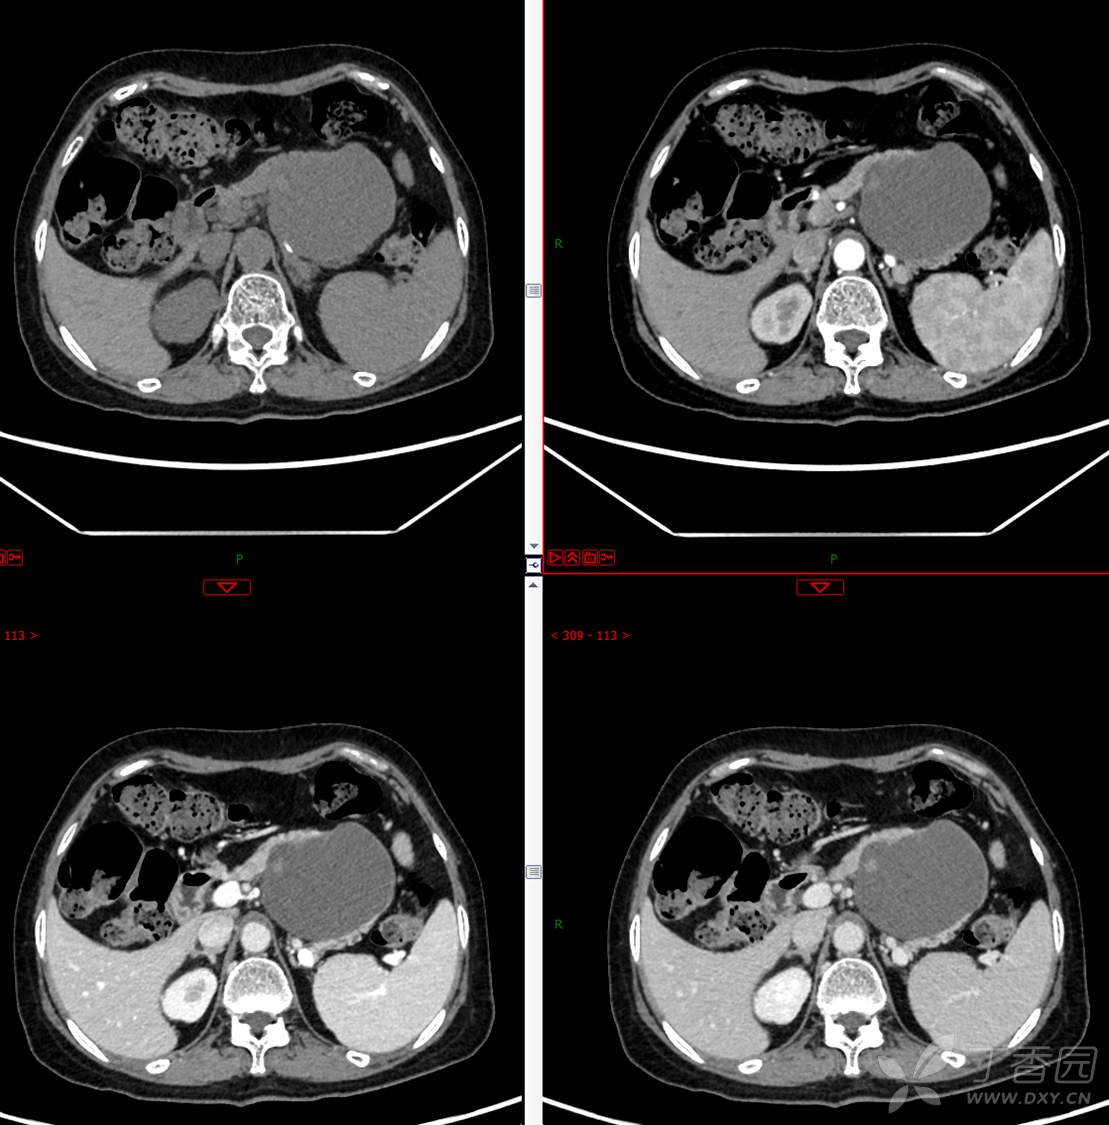

中老年女性胰腺占位,“奶奶瘤”or“妈妈瘤”?请分析领丁当!

主 诉:发现胰腺占位性病变3月

现病史:患者3月前就诊于**市人民医院行腹部增强CT发现胰尾占位性病变,无腹痛、腹胀,无恶心呕吐,无黄疸,无呕血黑便,无胸闷憋气,无寒战高热,未行特殊治疗